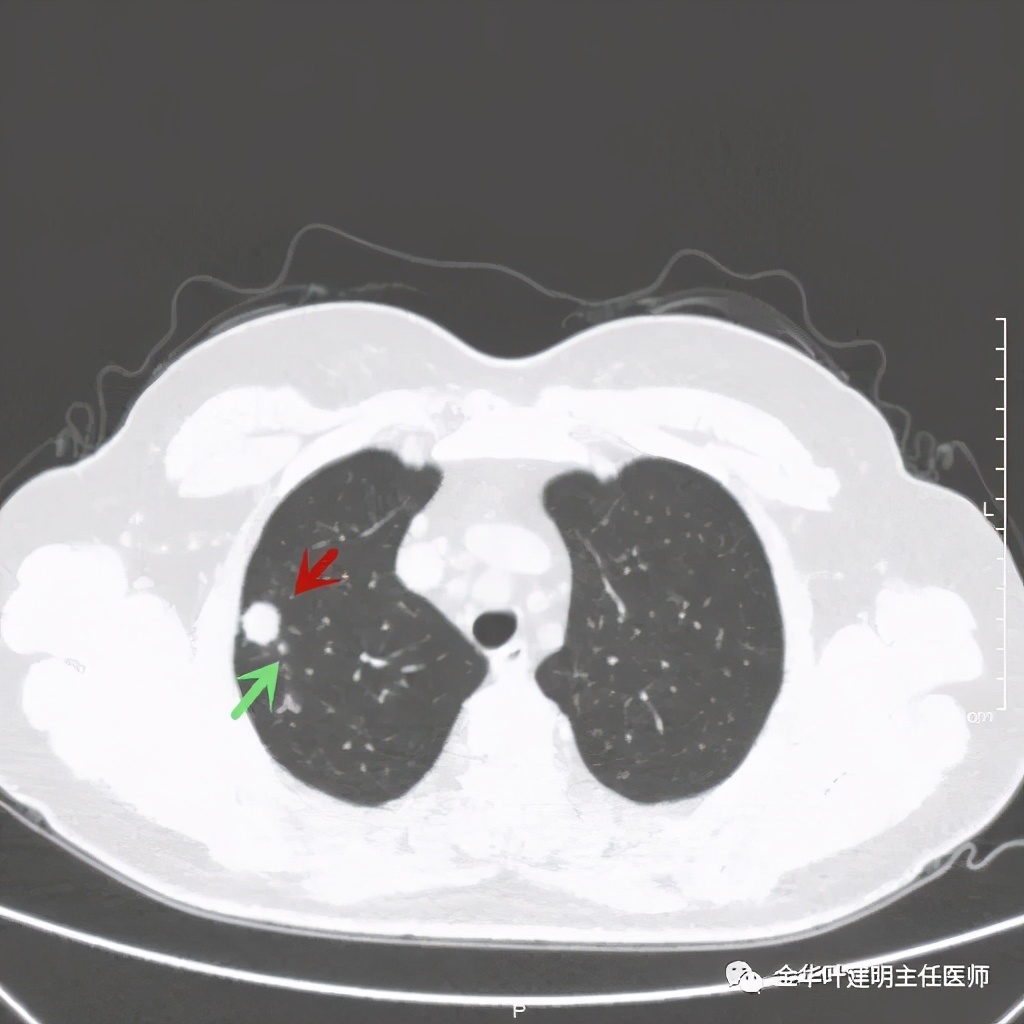

病灶比较光滑,密度高,旁边有小的卫星灶,不清爽

绿色箭头示主病灶边有小的实性微小结节,主病灶边缘非常光滑,没有毛刺、分叶等征

主病灶光滑,旁边有不清爽的小斑点状病灶